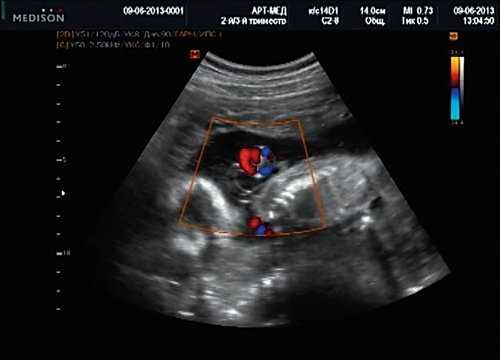

Тем не менее "базовое" УЗИ обычно дополняют исследованием в цветовом энергетическом допплеровском режиме с тщательным анализом для выявления атриовентрикулярного кровотока в четырех камерах сердца (рис. 6a) и в срезе через три сосуда и трахею (рис. 6b). Получив эти срезы, обычно можно успокоить родителей, исключив наличие тяжелых пороков сердца, таких как единственный желудочек, гипоплазия желудочков, полный дефект предсердно-желудочковой перегородки (atrioventricular septal defect - AVSD), атрезия аорты или легочной артерии, а также ряд аномалий расположения артерий.

Рис. 6. Эхокардиография плода на ранних сроках в цветовом энергетическом допплеровском режиме - визуализируются четыре камеры (a) и срез через три сосуда и трахею (b).